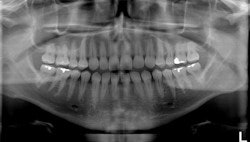

| The software also identifies regions of interest where 18 intraoral images would normally be taken, then extracts the images from a single panoramic x-ray to create an 18-image survey. |

In addition, the software can take a single panoramic x-ray and automatically divide it up to display as a full-mouth intraoral survey, extracting 18-20 regions of interest from a single pano image. This opens up the possibility of using this technique for posterior interproximal caries detection, he added.